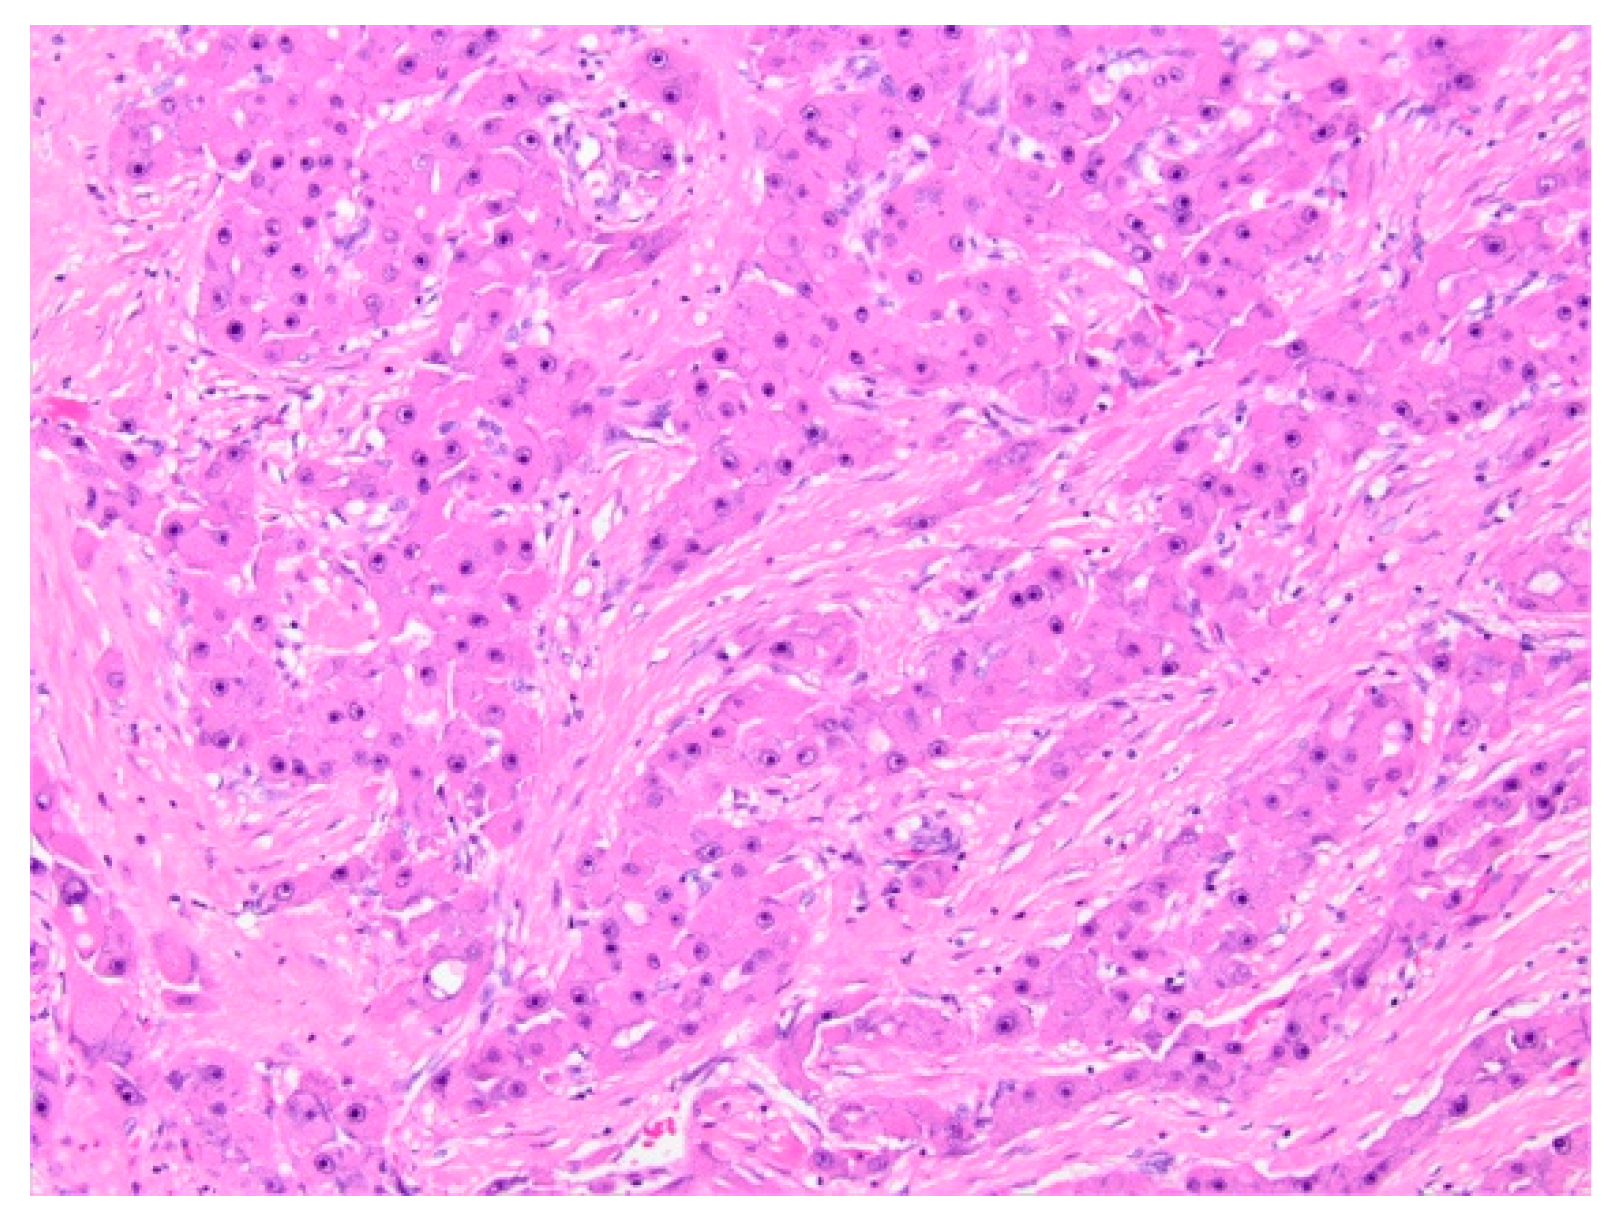

5.1.5. Histopathology and Immunohistochemistry

5.2.5. Histopathology and Immunohistochemistry